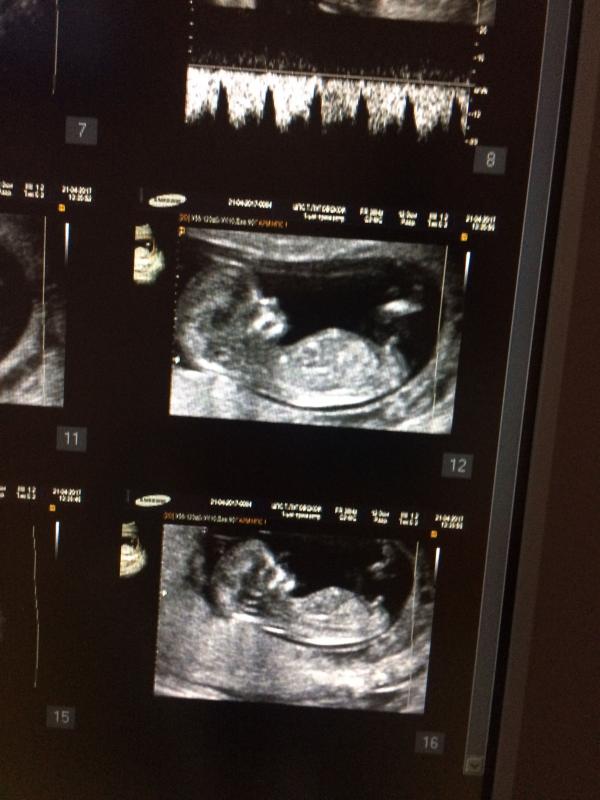

Девочки, сегодня были на первом скрининге. Хожу к крутому узисту, кто из Днепра знает, что Бут Г.Н. Никогда не ошибается, ну или очень редко. Так вот в прошлой беременности, она на 12 неделе определила, что у нас будет мальчик, так и есть. И сейчас сказала, что мы ждём сыночка. Это 90% из 100, говорит, что всего 10% таких "мальчиков" становиться девочками. Вопрос: У кого рождались детки противоположного пола от предсказанного? Расскажите!!!🙏🏻😩 Я очень люблю уже своего сыночка второго, но где то в глубине души все равно кроется надежда на девочку🙏🏻😍

@dianadiamond_ это мальчик(половой бугорок вверх)

@infinitium, Бут мне сегодня тоже объяснила как она видит, что у мальчиков бугорок направлен вверх, а у девочек горизонтально. 🤷🏼♀️